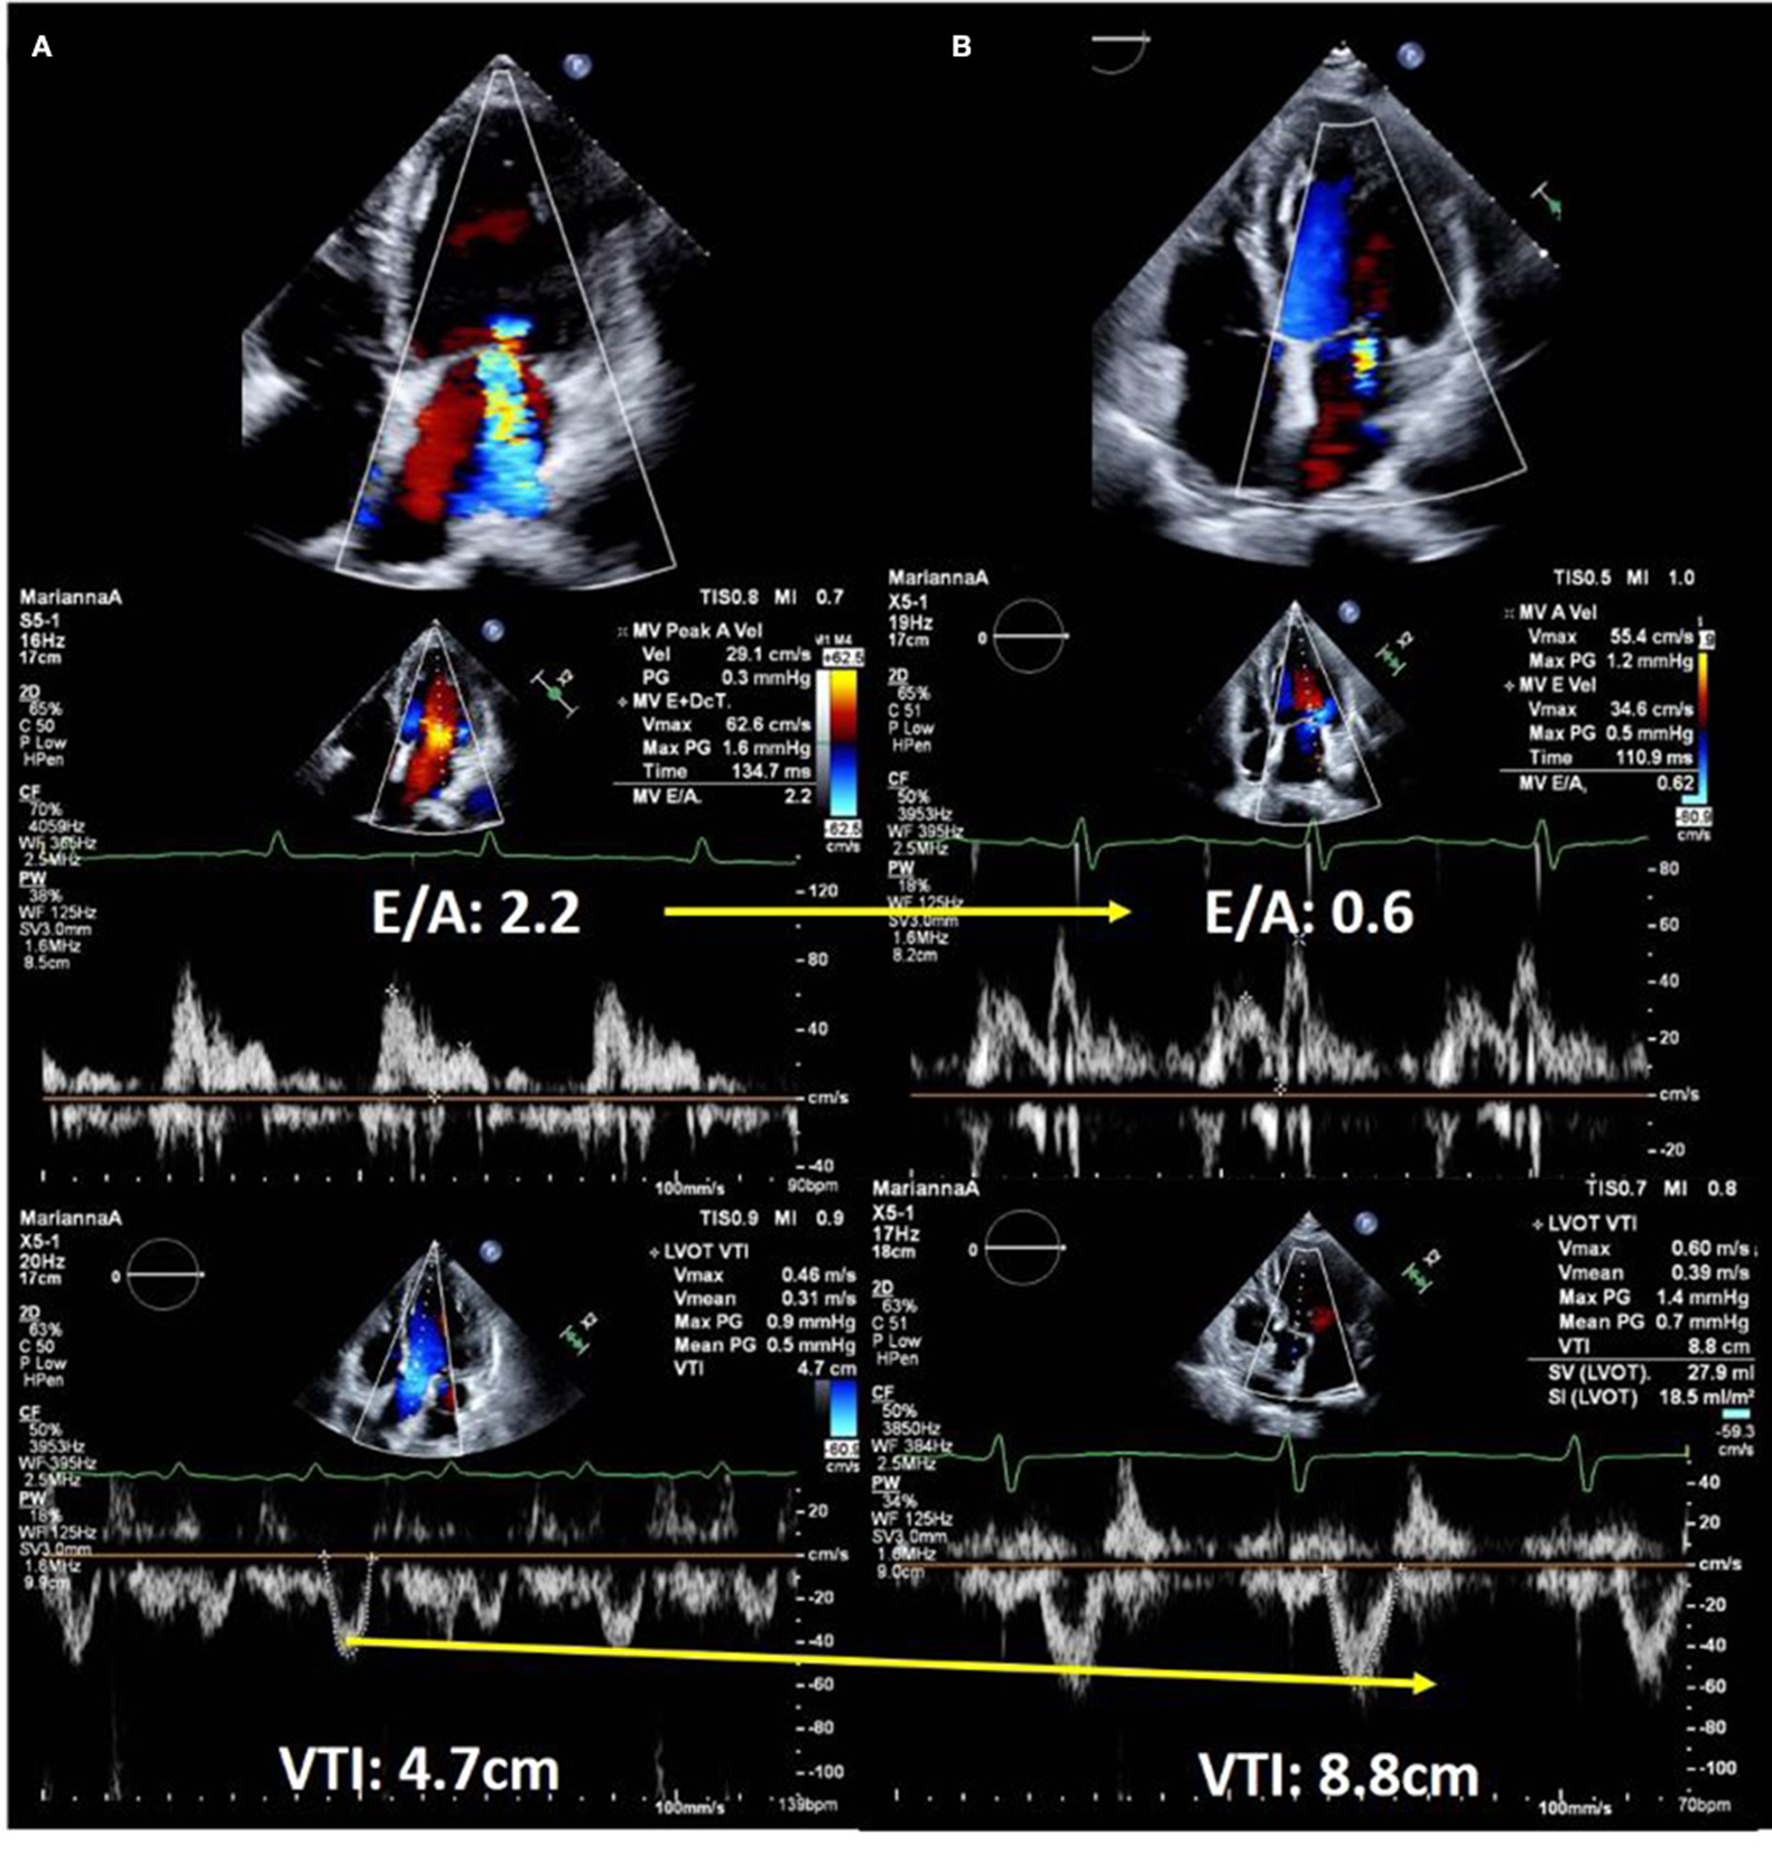

Echocardiography is performed for the evaluation of hemodynamics and estimation of left ventricular (LV) filling pressures as well as assessment of structural disorders in patients with acute HF (10, 1518). Forrester classification using pulmonary wedge pressure and cardiac index is useful for evaluating hemodynamics and determining treatment options for acute HF (19, 20). However, this requires an invasive procedure i.e., Swan-Ganz catheterization, and is, therefore, used less frequently. We can estimate the wedge pressure using echocardiography as well. Based on the American Society of Echocardiography guidelines, interpretation of the LV inflow pattern is simple and can be used to estimate the LV filling pressure. E/A of 2 or greater indicates that the LV filling pressure is increased (16). E/A is a simple and highly reproducible test that is useful in an emergency setting. However, during the 0.8 ~2 of E/A, patients with HFpEF and/or atrial fibrillation often suffer from an elevated left ventricular filling pressure. Making a diagnosis with an E/e' ≥13 on tissue Doppler imaging, a tricuspid flow velocity ≥2.8 m/s, and BNP may be helpful in daily clinical practice (21). Measurement of the velocity time integral (VTI) at the LV outflow tract (LVOT) is a simple and useful method of estimating the forward stroke volume and cardiac output (2225). LVOT VTI is useful for estimating not only the cardiac output but also the prognosis in HF with either preserved or reduced EF (25, 26). Changes in LV inflow pattern and LVOT VTI are useful for assessing treatment response. A case of acute HF with reduced EF is shown in Figure 2. It describes the case of a 58-year-old male with non-ischemic cardiomyopathy. Echocardiography showed severely impaired LVEF and severe secondary MR. On admission, LV inflow had a restrictive pattern and VTI was very low. The patient was determined to have Forrester classification IV HF, and he was started on vasopressor support. Repeat echocardiography was performed to confirm the response to treatment. The LV inflow pattern gradually improved, and LVOT VTI increased. Secondary MR improved dramatically in this case, and we could confirm the impact of HF treatment on echocardiography. Estimation of peak systolic pulmonary arterial pressure (SPAP) is important in clinical practice (2729). Most patients with ADHF had either passive or mixed pulmonary hypertension (30). There are two forms of pulmonary hypertension due to left-sided heart disease: post-capillary pulmonary hypertension, which is caused by the passive propagation of elevated left atrial or pulmonary venous pressures into the pulmonary arteries, and pre-capillary pulmonary hypertension, which is caused by pulmonary artery remodeling and further pulmonary artery pressure elevation. Combined pre- and post-capillary pulmonary hypertension has been shown to have a worse prognosis than passive pulmonary hypertension. It has been suggested that therapeutic intervention is necessary for patients with reactive pulmonary hypertension, and it is critical to consider this diagnosis and subsequent management strategies for patients with acute heart failure. SPAP is estimated from the peak velocity of the tricuspid regurgitation jet and right atrial pressure (28, 30). A correlation between echocardiographic and invasive assessment of SPAP in patients with acute HF has been reported, and echocardiography is used to assess SPAP in clinical practice (27). A Japanese multicenter study reported that changes in tricuspid regurgitation peak gradient (TRPG) had additive value in predicting the prognosis of worsening renal failure in acute HF. Worsening renal failure with increased TRPG levels is associated with a poor prognosis (31).

FIGURE 2

www.frontiersin.org

Figure 2. Echocardiographic images of a 58-year-old man with dilated cardiomyopathy showing response to heart failure therapy. (A) On admission. Upper panel shows severe secondary mitral regurgitation with dilated left ventricle. Middle panel shows restrictive left ventricular inflow pattern and velocity time integral of only 4.7 cm, which suggested low forward cardiac output. (B) After 14 days of hospitalization. Color Doppler echocardiography shows a significant reduction in mitral regurgitation (upper panel). Doppler echocardiography showed decreased left ventricular filling pressure (middle panel) and significantly improved forward cardiac output (lower panel).